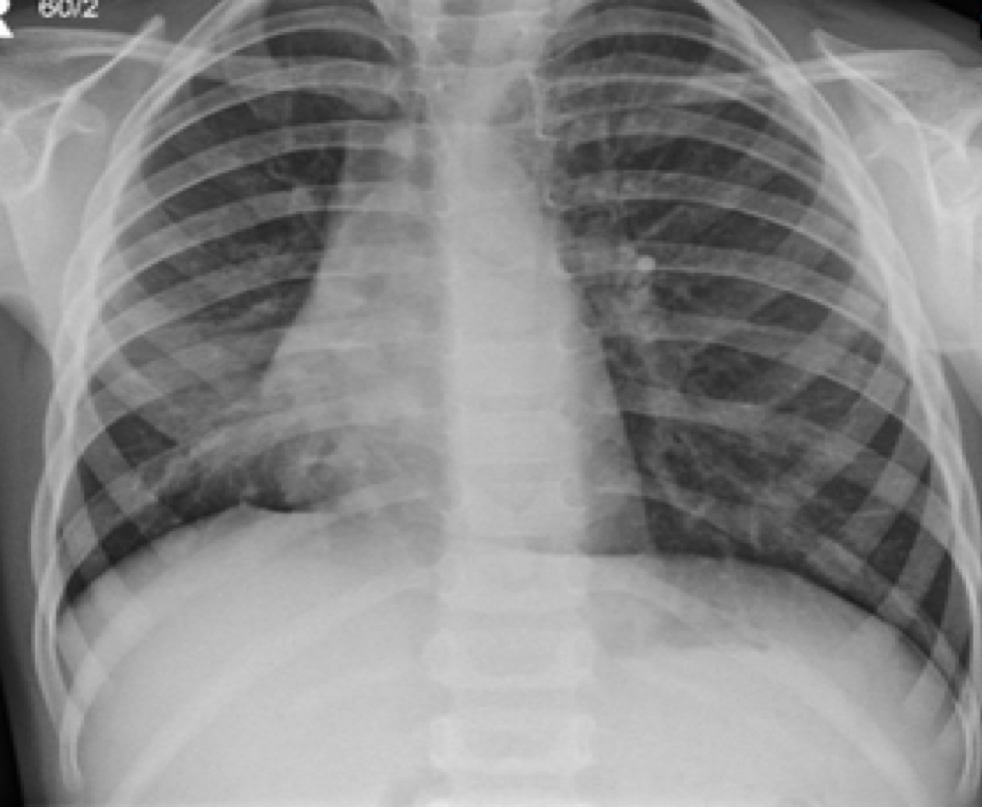

What is this showing?

AP errect

LUL collapse- collapses anteirorly becoming a thin sheet of tissue –> “Veil sign”

Loss of silhouette sign of aortic knuckle

General opacity on the left